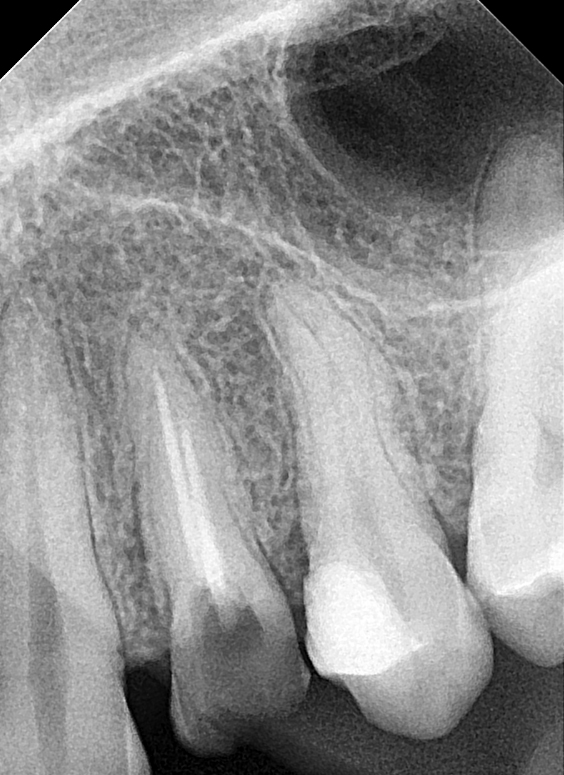

RX DENTAR

Sistem de ultima generatie, cu control automat al timpului de expunere, in functie de programul selectat; multiple programe presetate, in functie de detaliile anatomice ale pacientului, posibilitate operare cu senzor digital sau film.